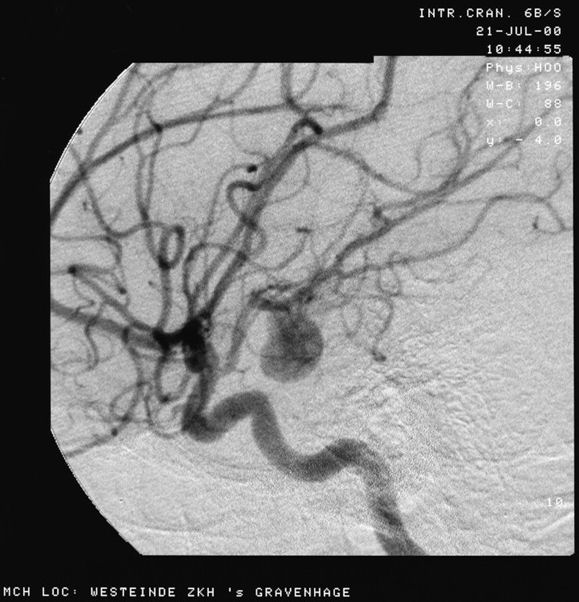

Angiograph of an aneurysm in a cerebral artery

Source: Aneurysem.jpg Date: 21 Julie 2000 Author: Lucien Monfils Licence: Creative Commons Attribution-Share Alike 3.0 Unported